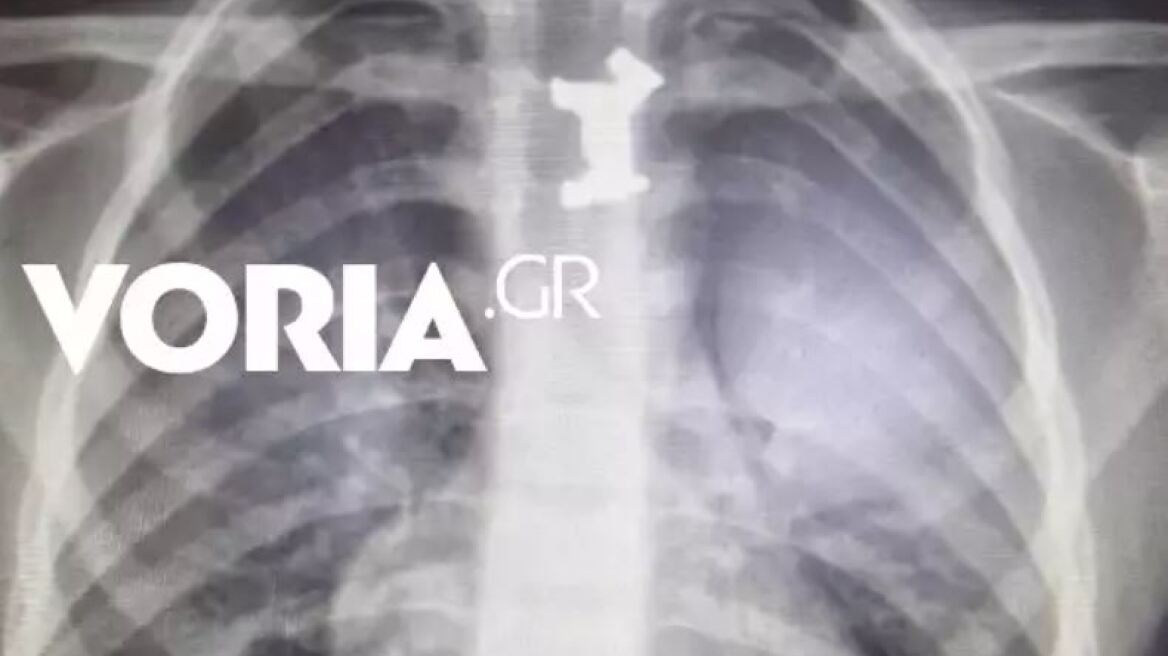

Σύμφωνα με πληροφορίες της voria, μετά από τις ακτινογραφίες διαπιστώθηκε πως το παιδί είχε καταπιεί ένα μεταλλικό σκυλάκι από επιτραπέζιο παιχνίδι που έπρεπε να αφαιρεθεί άμεσα, καθώς ήταν σε αρκετά δύσκολο σημείο.

Αφότου έγιναν όλες οι απαραίτητες εξετάσεις, αλλά και μετά από εκτίμηση παιδο-ΩΡΛ, υπεβλήθη σε οισοφαγοσκόπηση υπό γενική αναισθησία για την αφαίρεσή του από τον οισοφάγο.

Οι γιατροί είναι ικανοποιημένοι από την επιτυχημένη απαιτητική επέμβαση και την άμεση απομάκρυνση του αντικειμένου. Το παιδάκι είναι καλά στην υγεία του και νοσηλεύεται στην Παιδιατρική Κλινική.